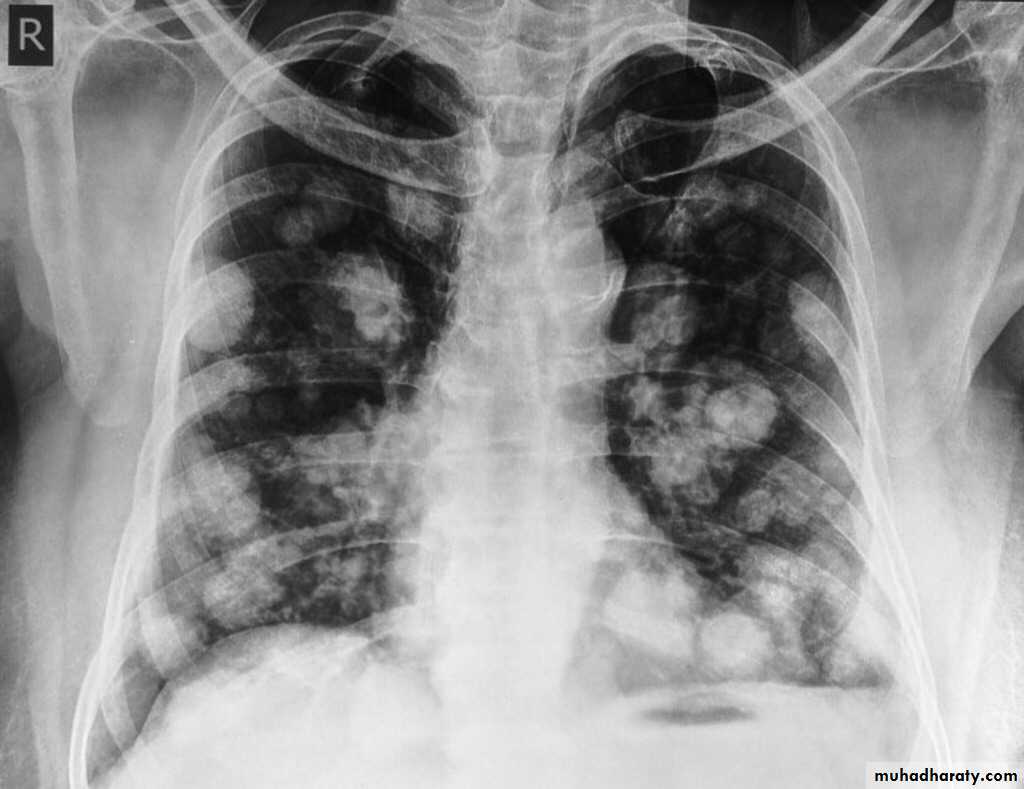

Secondary tumors in the lung

The lung is a common site of secodary's due to the high blood supply.Secondaries reach the lung by blood from GIT, Female G.T., bone breast giving rise to cannon ball metastasis etc